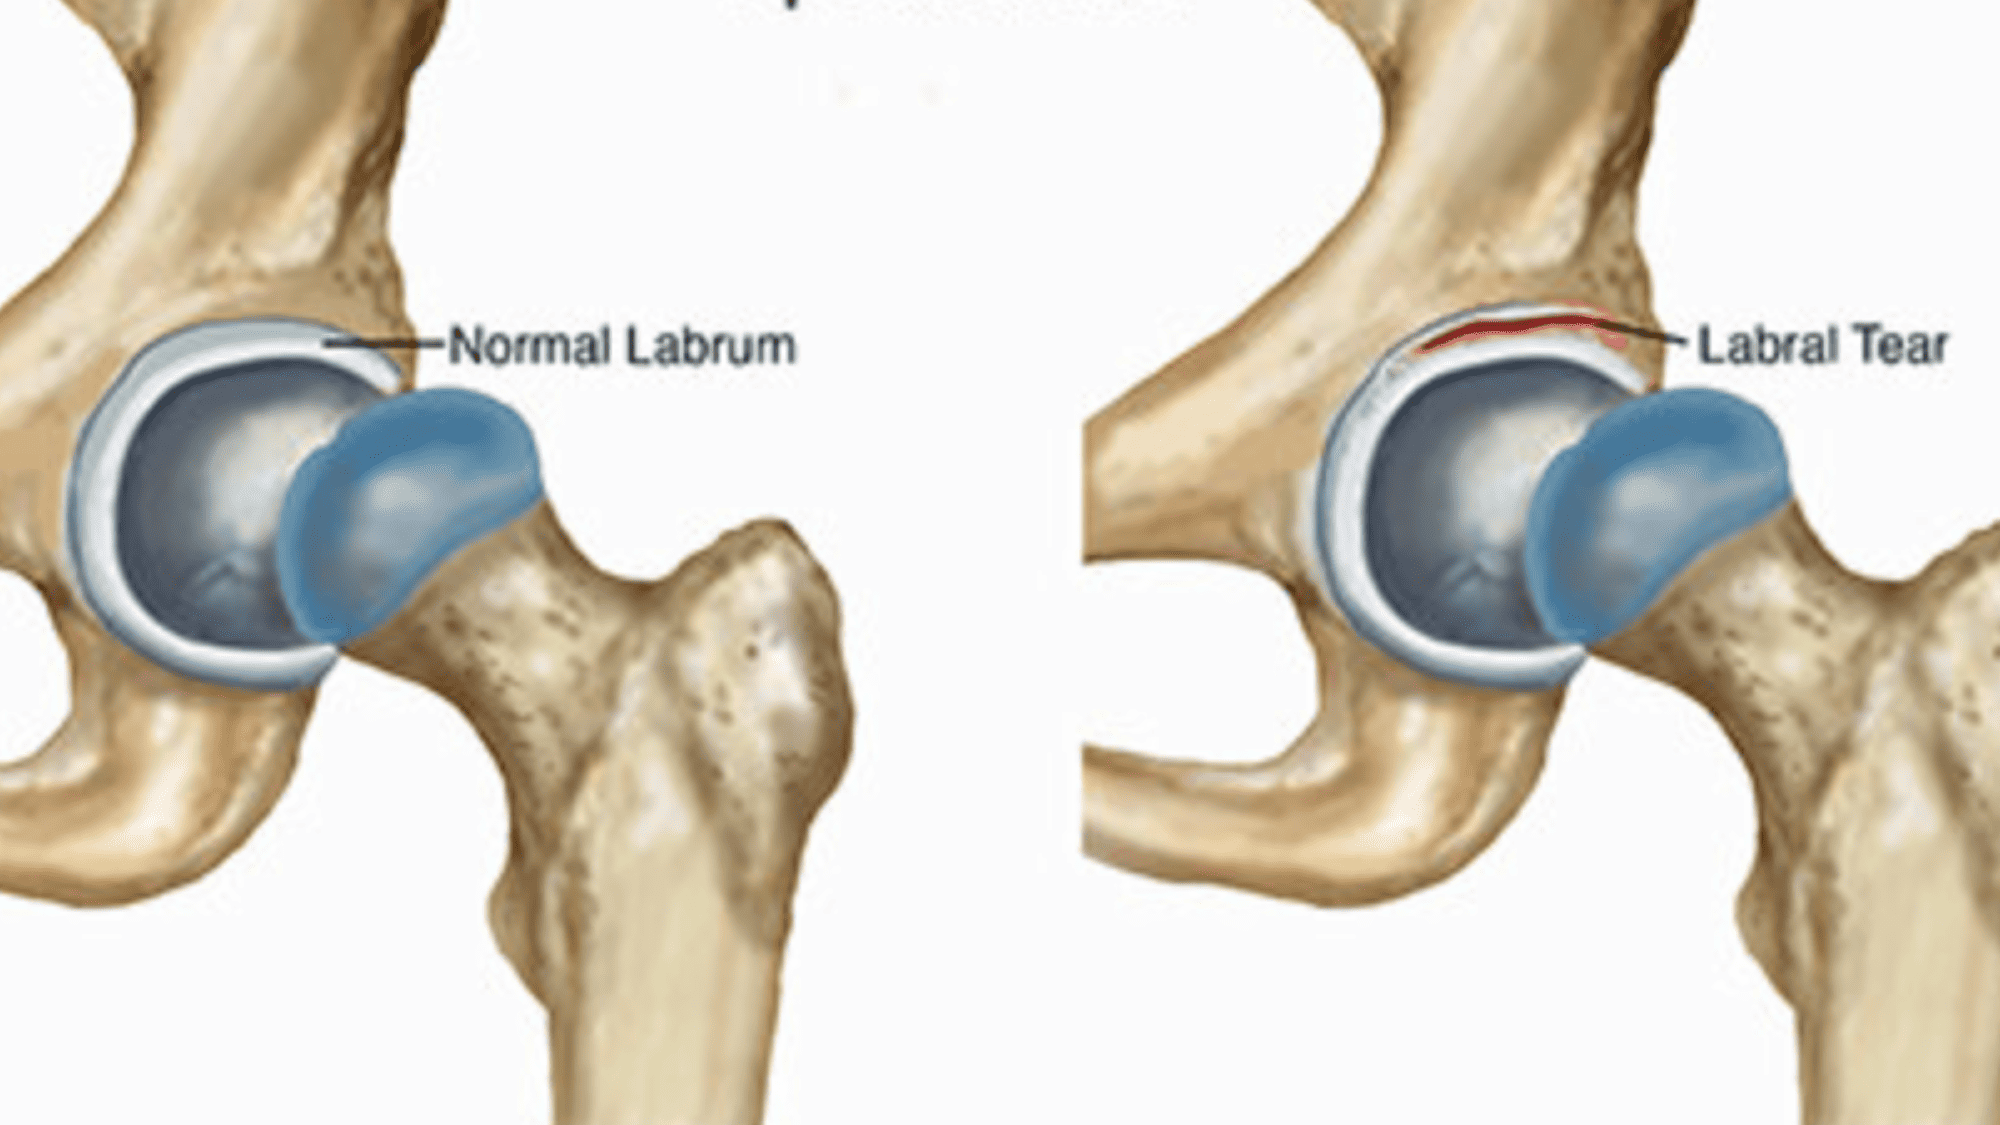

Hip Labral Tear

Hip Impingement